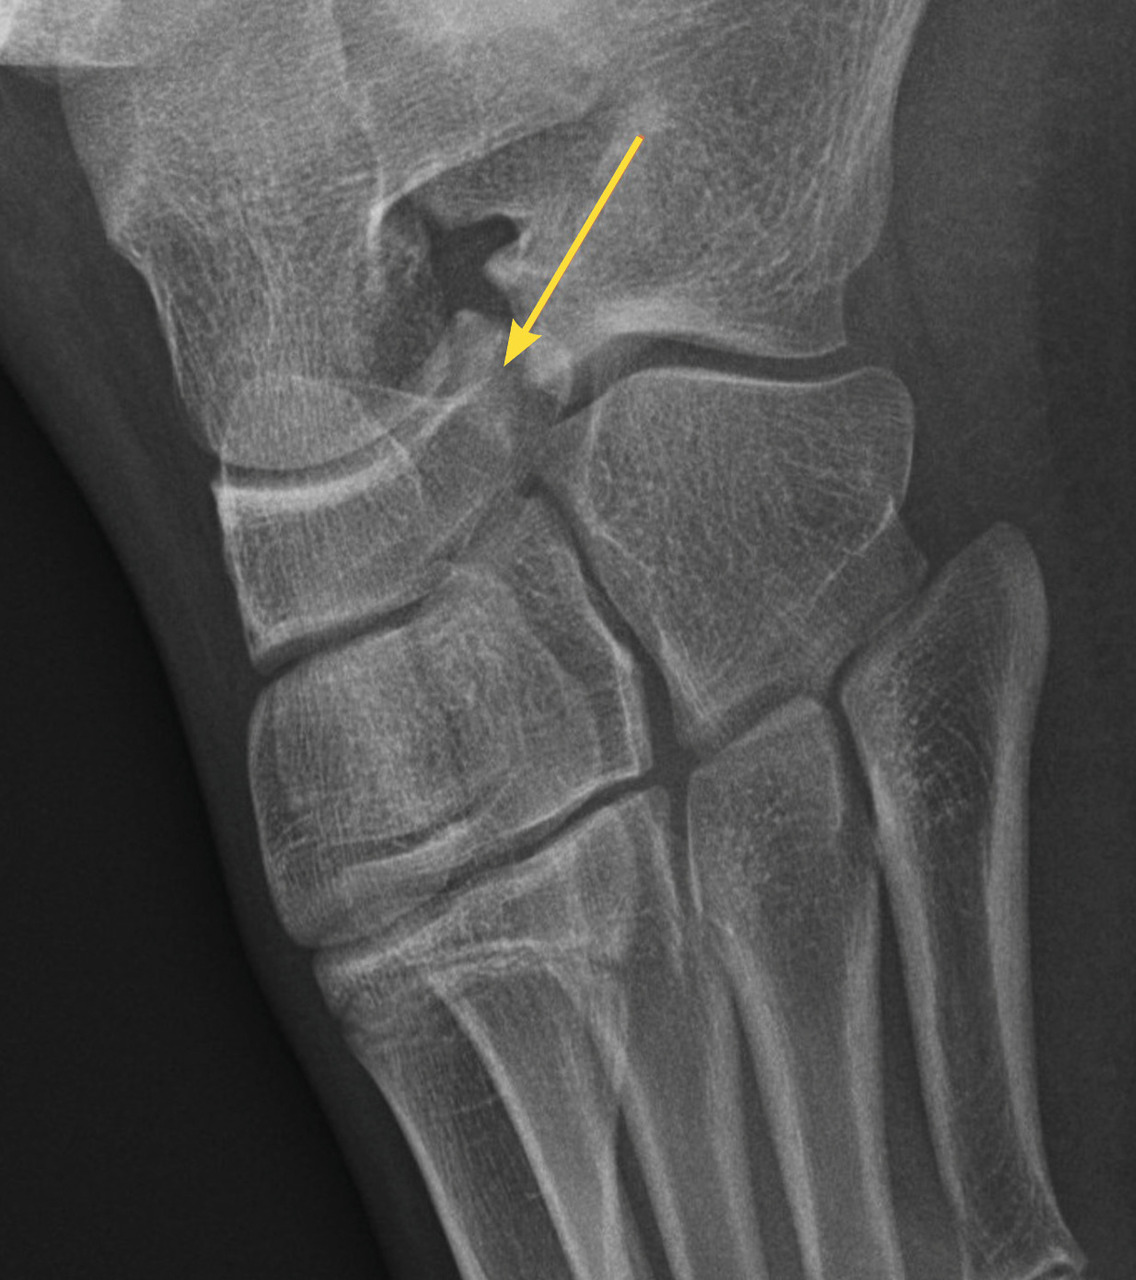

Il n’y a pas de consensus sur des tests cliniques (critères d’Otta­wa…) car ils ont une faible sensi­bilité sur les fractures peu ou non déplacées.4 En cas de doute à l’examen clinique, il est donc nécessaire de demander au moins deux incidences : face et profil. Par ailleurs, la cheville étant initialement une matrice cartilagineuse qui va pro­gressivement s’ossifier, la lecture des ­radiographies est parfois difficile chez l’enfant, dont les cartilages de croissance sont encore visibles (fig. 1). Dans environ 20 % des traumatismes, une fracture est retrouvée, notamment des avulsions de la pointe de la fibula, signe d’entorse grave, dont la prise en charge doit être rigoureuse pour éviter des instabilités chroniques.

Le diagnostic différentiel est principalement constitué par les fractures. Celles-ci sont spécifiques du fait des particularités de l’os pédiatrique, et le tableau clinique n’est pas toujours aussi flagrant que chez l’adulte. Il n’est pas rare de voir des enfants conserver un appui partiel sur des chevilles fracturées. Dans environ 20 % des traumatismes en inversion, il existe une avulsion de la pointe de la fibula8 (fig. 2), qui doit être recherchée et traitée par une botte en résine durant un mois, quel que soit l’âge. Les décollements épiphysaires de la malléole externe sont beaucoup plus rares que ce qui a longtemps été cru6, et leur pronostic fonctionnel semble bon quel que soit le traitement.